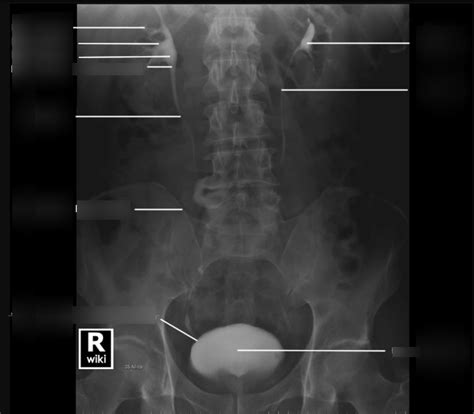

Hey guys! Let’s dive into the fascinating world of IVP anatomy. IVP, or Intravenous Pyelogram, is a radiological procedure used to visualize the urinary system. To really understand what’s going on during an IVP, it’s super important to have a solid grasp of the anatomy involved. So, let’s break it down in a way that’s easy to digest. We’ll explore each component, its function, and why it matters for a successful and informative IVP. Knowing your anatomy is half the battle, right? So, buckle up, and let’s get started!

The kidneys are bean-shaped organs located in the abdominal cavity , towards the back. Most people have two kidneys, sitting on either side of the spine. These incredible organs are the primary filters of your blood. Blood enters the kidneys through the renal arteries , and inside, it’s filtered through tiny structures called nephrons. Each kidney contains about a million nephrons! These nephrons remove waste products like urea, creatinine, and excess salts, while also reabsorbing essential substances like glucose, amino acids, and water back into the bloodstream. The filtered waste, now called urine, is then collected and channeled out. The purified blood exits the kidneys through the renal veins . The kidneys aren’t just about filtration; they also play a vital role in regulating blood pressure, producing hormones like erythropoietin (which stimulates red blood cell production), and maintaining electrolyte balance. Proper kidney function is essential for overall health, and any issues here can have widespread effects on the body. During an IVP, the contrast dye is filtered by the kidneys, allowing radiologists to visualize their structure and function. This helps in identifying any abnormalities, such as blockages, tumors, or structural issues. Understanding the kidney’s anatomy – its outer cortex, inner medulla, and the renal pelvis – is key to interpreting IVP images effectively.

The ureters are muscular tubes that connect the kidneys to the bladder. Think of them as the urine’s personal delivery system. There are two ureters, one for each kidney. These tubes are about 25-30 cm long and use peristaltic contractions (wave-like muscle movements) to push urine down from the kidneys to the bladder. The ureters enter the bladder at an angle, which helps prevent urine from flowing back up towards the kidneys – a condition called vesicoureteral reflux. This one-way flow is crucial for preventing infections and maintaining the health of the kidneys. The walls of the ureters are made up of three layers: an inner mucous membrane, a middle muscular layer, and an outer fibrous layer. This structure allows them to contract and relax, effectively moving urine along. In an IVP, the ureters are visualized as the contrast dye travels through them. Radiologists look for any constrictions, blockages, or abnormalities in their shape and size. Stones, tumors, or external compression can all affect the ureters and be detected during an IVP. Understanding the normal anatomy of the ureters is essential for identifying any deviations that could indicate underlying pathology.

The bladder is a hollow, muscular organ located in the pelvis . It’s designed to store urine until you’re ready to release it. Think of it as your body’s temporary holding tank! The bladder can expand significantly to accommodate varying amounts of urine. Its walls are made of the detrusor muscle, which contracts to expel urine during urination. The inside of the bladder is lined with a special type of tissue called transitional epithelium, which allows the bladder to stretch without damage. The bladder’s capacity varies from person to person but typically holds around 400-600 ml of urine. When the bladder fills, stretch receptors in its walls send signals to the brain, creating the urge to urinate. When you’re ready to go, the detrusor muscle contracts, and the internal and external urethral sphincters relax, allowing urine to flow out through the urethra. During an IVP, the bladder is visualized as it fills with contrast dye. Radiologists assess its shape, size, and wall thickness. Abnormalities like tumors, bladder stones, or diverticula (pouches in the bladder wall) can be detected. The ability of the bladder to empty completely can also be evaluated. Understanding the normal anatomy of the bladder and its filling and emptying mechanisms is crucial for interpreting IVP images and identifying any functional or structural issues.

Contrast dye is a special substance that’s injected into your bloodstream during an IVP. It contains iodine, which is opaque to X-rays. This means it blocks X-rays and shows up brightly on the images, making the urinary structures much easier to see. As the contrast dye is filtered by the kidneys and travels through the ureters and into the bladder, it outlines these structures, allowing radiologists to visualize their shape, size, and any abnormalities. The timing of the X-ray images is crucial. Images are taken at specific intervals to capture the contrast dye as it moves through each part of the urinary system. Early images show the kidneys filling with contrast, while later images show the ureters and bladder. The radiologist carefully examines these images to look for any signs of blockage, narrowing, tumors, or other abnormalities. The use of contrast dye is what makes the IVP such a valuable diagnostic tool. Without it, the urinary structures would be difficult to distinguish from the surrounding tissues.